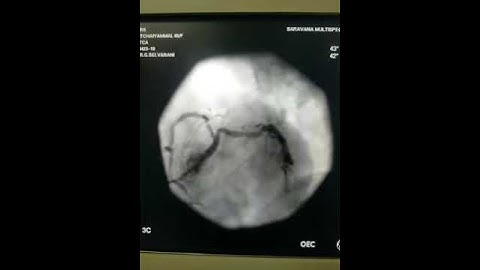

ostial LAD CTO